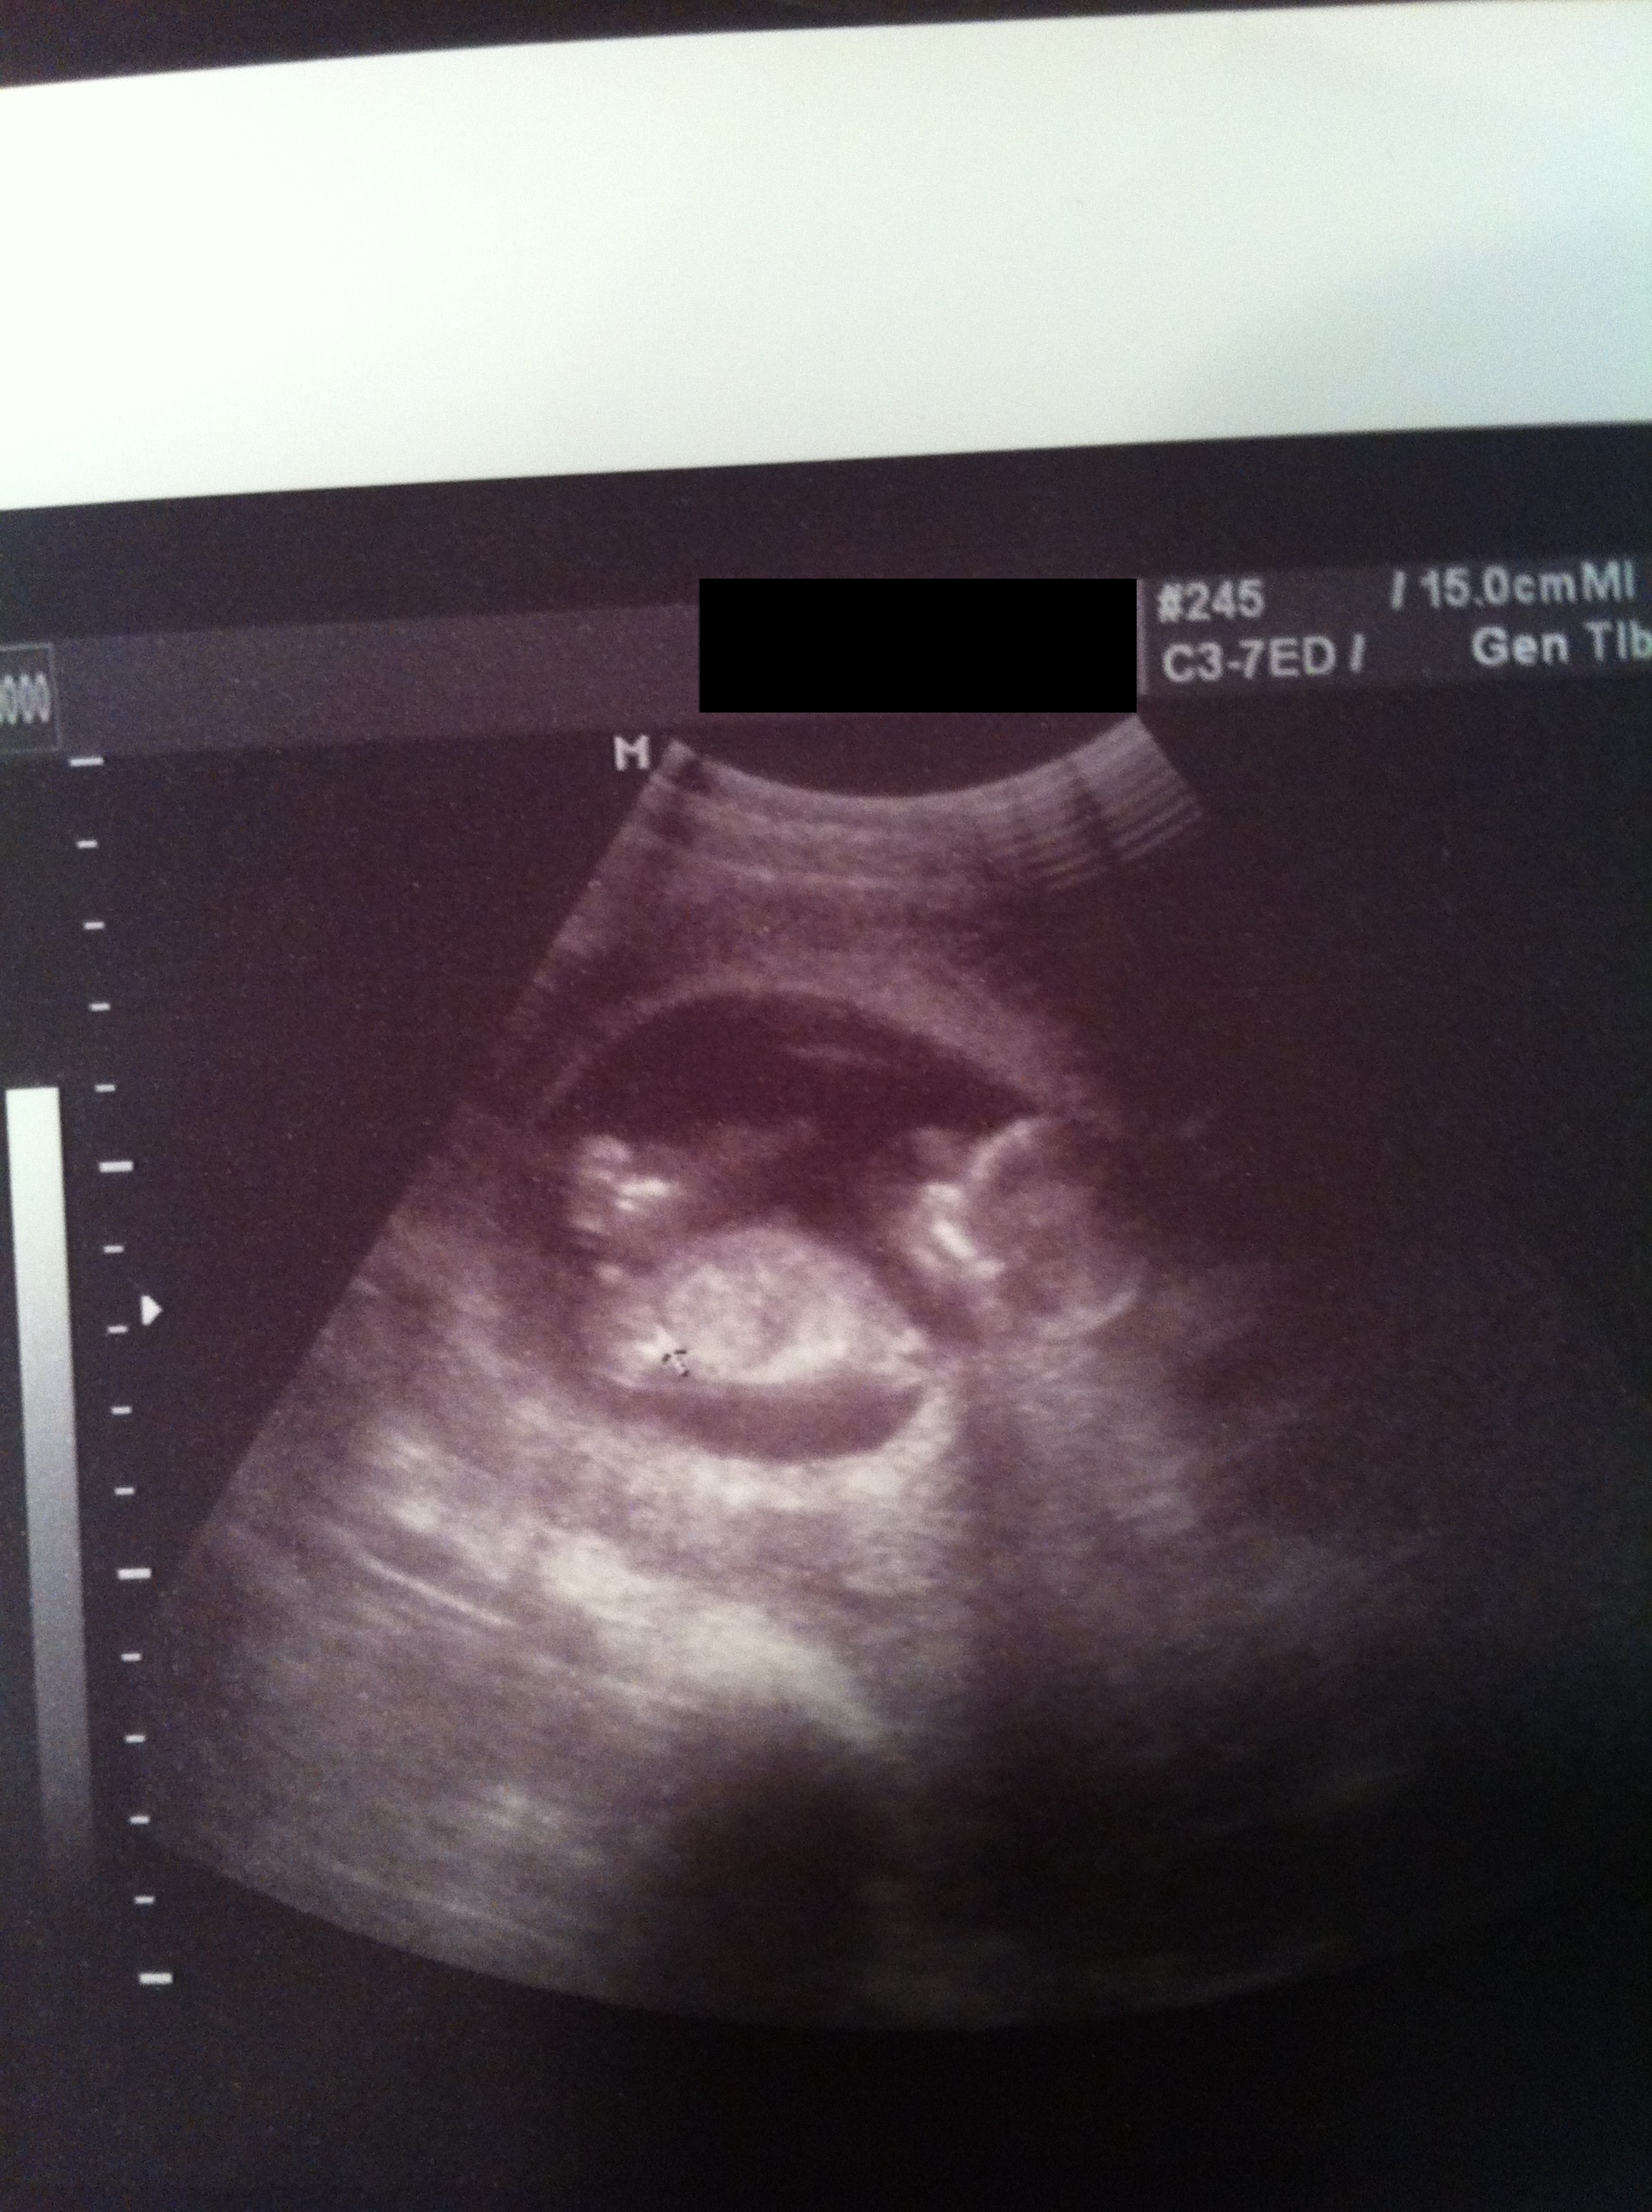

13w1Day Nub Theory!! Please Guess !!

I have posted this photo on another site as well and have got about 70/30 guesses for boy (most of these were a slight lean but boy nonetheless). I am soooo hoping for a girl as this is my last chance for one. Just wanted to hear some more opinions. I keep flipping back and forth I think because the spine kind of curves up a bit at the end so when i look at that line it is parallel to the nub but when looking at the baby's back overall the nub is slightly inclined (hopefully that makes sense). I've also been told it's not a huge nub for a boy being that this is a 13week ultrasound. Baby measured 13w2days. I should find out what I am having in a month.

Any guesses would be appreciated. Thanks so much x